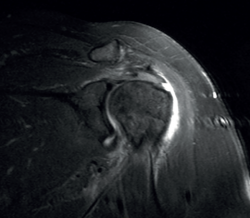

Una lesión es clasificada como de espesor parcial si, en una secuencia T2, una señal anormal de intensidad de fluido se extiende a través de una porción del tendón sin violar su espesor completo (Figura 7). Estas lesiones pueden ser bursales o articulares, siendo las articulares las más frecuentes. Existe la posibilidad de que el espesor de la lesión parcial esté ocupado por tejido cicatricial o de granulación, dificultando el diagnóstico. Se ha sugerido que el uso de la artro-RMN en posición de ABER (abducción + rotación externa) puede mejorar el diagnóstico y la tipificación de estas lesiones(34). Según Ellman(35), las lesiones de espesor parcial de pueden clasificar en 3 grados: grado I si la profundidad de la misma es < 3 mm; grado II si la profundidad es de 3 a 6 mm; y grado III si es > 6 mm. Teniendo en cuenta que un supraespinoso sano tiene un grosor de entre 10 y 12 mm, las de grado III afectan a más del 50% del espesor. Las lesiones intrasustancia se presentan con una señal de tipo fluido en el espesor del tendón sin extensión a la bursa o al espacio articular.

Figura 7. Rotura de espesor parcial bursal del supraespinoso en visión por resonancia magnética nuclear.